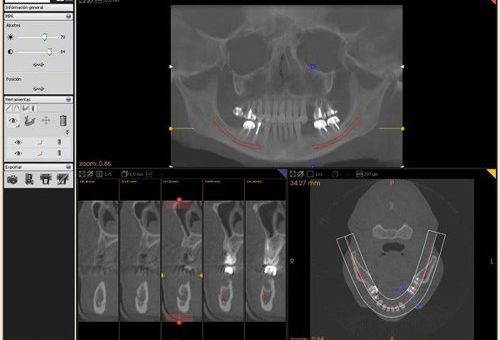

Se trata de un escáner intraoral que obtiene imágenes en tres dimensiones de la mandíbula y cada una de las piezas dentales y huesos.

Las imágenes que se obtienen, mediante cortes y rayos X, nos permiten hacernos una idea muy clara de la situación de las piezas dentarias, sus características, su estado y las características de los tejidos blandos que las rodean.

La precisión de esta prueba permite observar las estructuras dentales y maxilares en tres dimensiones, lo que facilita el diagnóstico y tratamiento

La radiografía Dentascan 3D permite ver, al detalle, cualquier estructura gracias a su procedimiento computarizado que une imágenes tridimensionales.